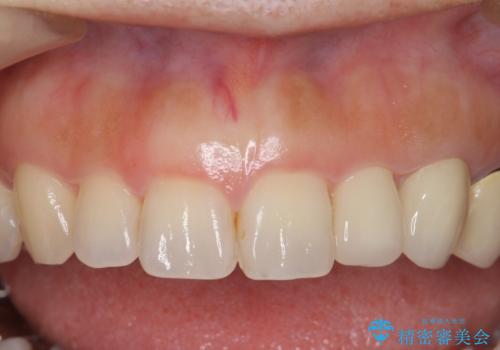

前歯が左右対称じゃない 保険の被せ物をきれいにしたい ホワイトニング併用

小さい前歯は、反対側と合わせた形にしました。

左右対称に仕上げることができ、治療には非常に満足していただきました。